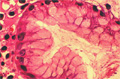

- ★(4)Gastritis (acute gastritis)

Gross appearance: Endoscopic view of AGML (acute gastric mucosal lesion). There is erosive gastritis demonstrated by multiple erosive, hemorrhagic foci in the gastric pylorus (arrow).